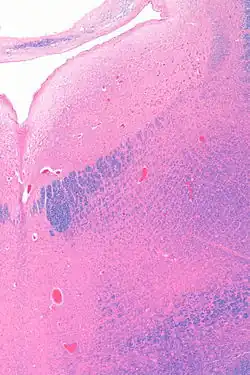

Anatomy

The locus coeruleus (LC) is located in the posterior area of the rostral pons in the lateral floor of the fourth ventricle. It is composed of mostly medium-size neurons. Melanin granules inside the neurons contribute to its blue colour. Thus, it is also known as the blue nucleus, or the nucleus pigmentosus pontis (heavily pigmented pontine nucleus).[5] The neuromelanin is formed by the polymerization of norepinephrine and is analogous to the black dopamine-based neuromelanin in the substantia nigra.

In adult human males,[a] the locus coeruleus has 22,000 to 51,000 total pigmented neurons that range in volume from 31,000 to 60,000 μm3.[6]